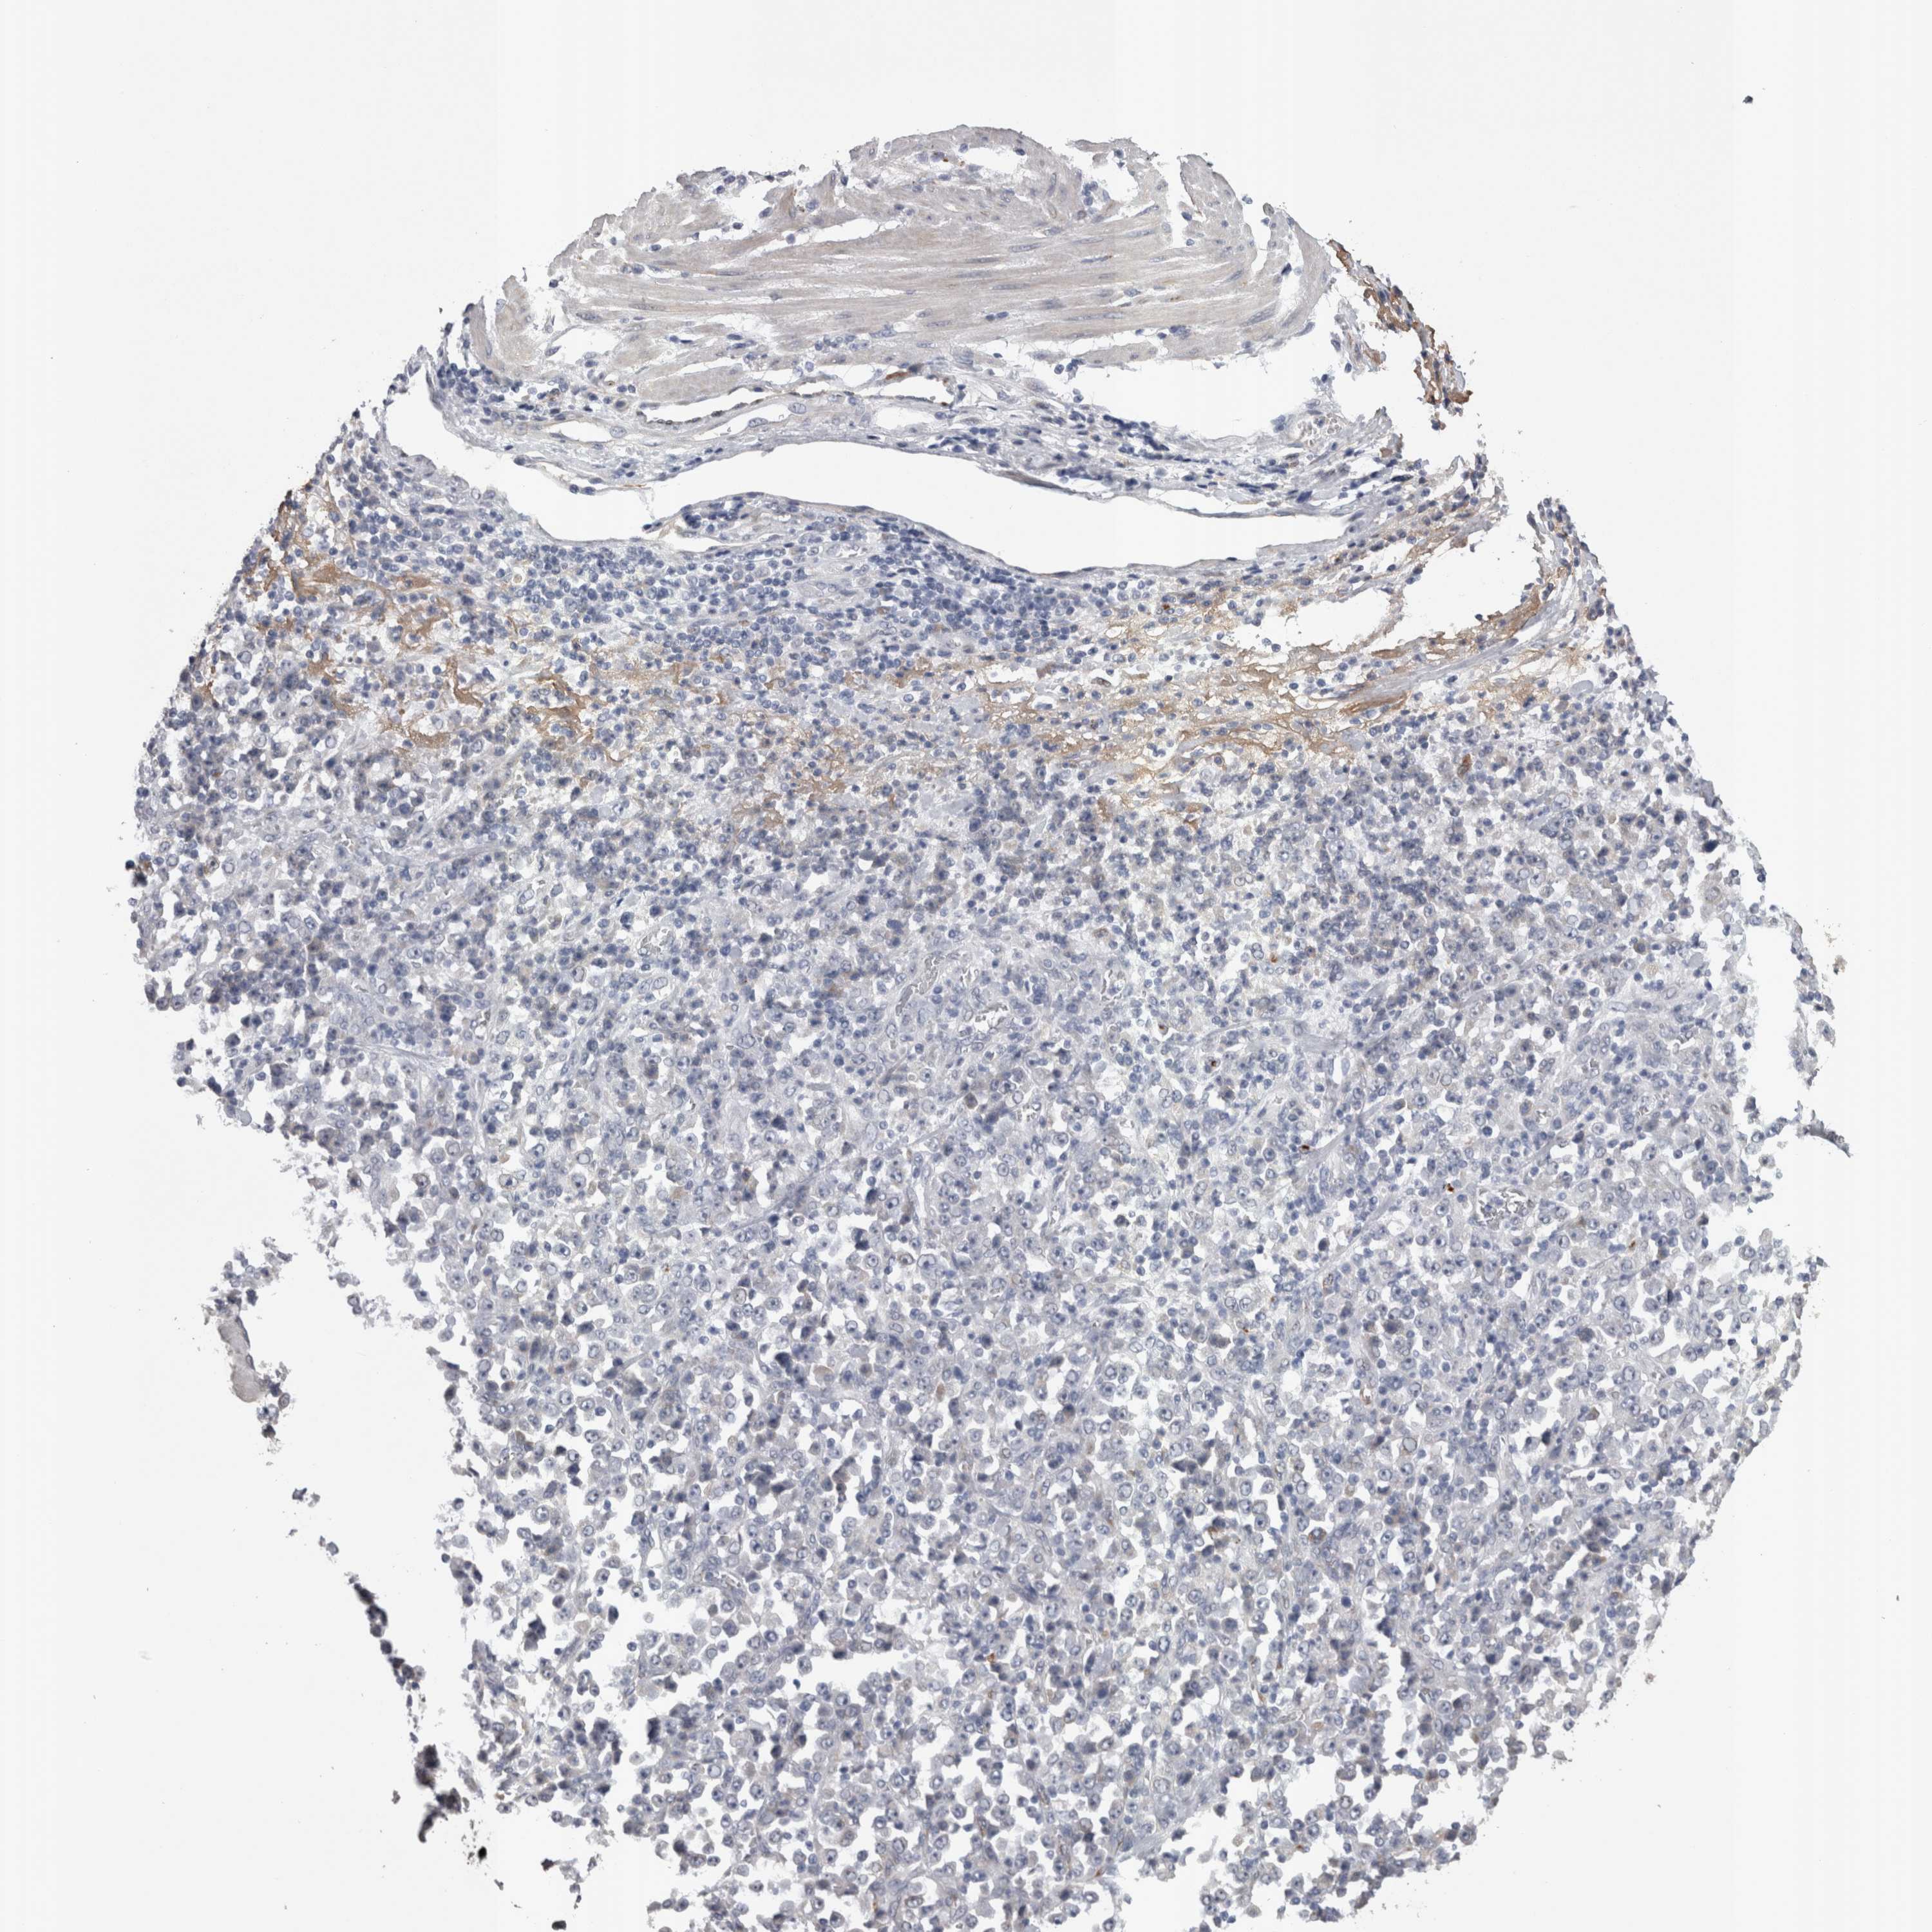

STOMACH CANCER - Protein expressioni

A mouse-over function shows sample information and annotation data. Click on an image to view it in a full screen mode. Samples can be filtered based on level of antibody staining by selecting one or several of the following categories: high, medium, low and not detected. The assay and annotation is described here.

Note that samples used for immunohistochemistry by the Human Protein Atlas do not correspond to samples in the TCGA dataset.

Antibody stainingi

Antibody staining in the annotated cell types in the current human tissue is reported as not detected, low, medium, or high, based on conventional immunohistochemistry profiling in selected tissues. This score is based on the combination of the staining intensity and fraction of stained cells.

Each image is clickable and will lead to virtual microscopy that enables deeper exploration of all samples and also displays staining intensity scores, fraction scores and subcellular localization as well as patient and tissue information for each sample.

Antibody HPA023918

Antibody CAB018625

Staining

High

Medium

Low

Not detected

Intensity

Strong

Moderate

Weak

Negative

Quantity

>75%

75%-25%

<25%

None

Location

Nuclear

Cytoplasmic/membranous

Cytoplasmic/membranous,nuclear

Adenocarcinoma, NOS